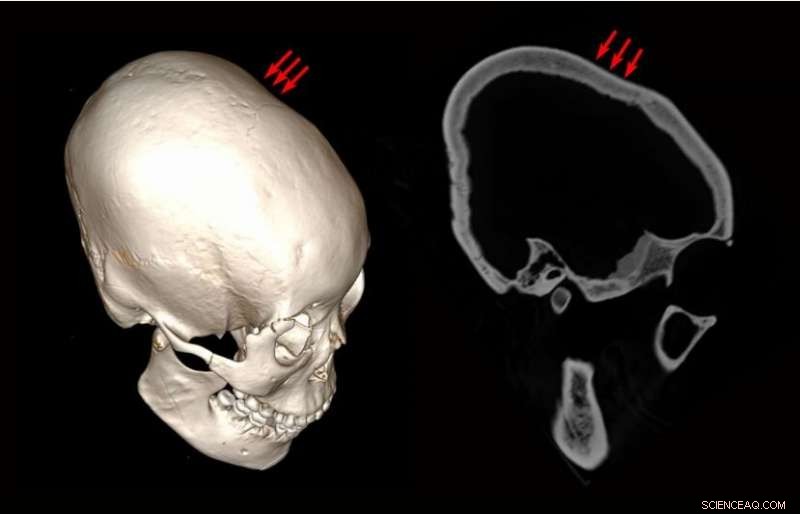

“Postcoronal depression” displayed by M45. A depression locates slightly posterior to the coronal suture on both parietal bones. The increase of the thickness of the diploë in the frontal and parietal bone is visible. Credit: American Journal of Physical Anthropology (2019). DOI: 10.1002/ajpa.23888

In this new effort, the researchers were studying skeletal remains removed from a site called Houtaomuga. The site is believed to have been an ancient Chinese tomb—archaeologists worked at the site from 2011 to 2015. The skeletons were all in a vertically shaped tomb, and there were no obvious gender biases for cranial modification. Twenty-five skeletons were found in all, 11 of which had evidence of intentional cranial modification. Four of the skulls were from adult males, one was from an adult female, and the rest were from children. The bones were not placed in the tomb at the same time, however, they were interred over the course of 7,000 years, from 12,000 to 5,000 years ago.